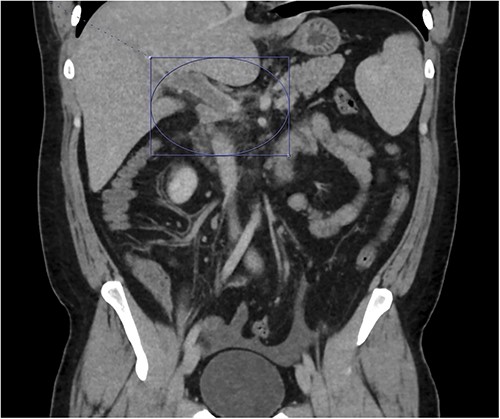

Thrombosis can be seen extending into the mesenteric venous system as well as the intrahepatic portal veins; associated mesenteritis and abdominal ascites (not well visualized) are also seen.

Patient was admitted to the surgical service and started on broad-spectrum IV antibiotics (piperacillin–tazobactam) and was made nil per os. He was resuscitated intravenously with 2 l of crystalloid. Given the thrombosis of his PV and SMV, the patient was initiated on systemic anticoagulation with IV heparin which achieved therapeutic dosing within 24 hours. Over the course of the next few days, his abdominal pain and tachycardia improved. Interval CT abdomen/pelvis scan 5 days from presentation demonstrated progression of the thrombus to involve lobar, segmental, and subsegmental portal venous branches as well as the splenic vein distal to the portosplenic confluence (Fig. 2).